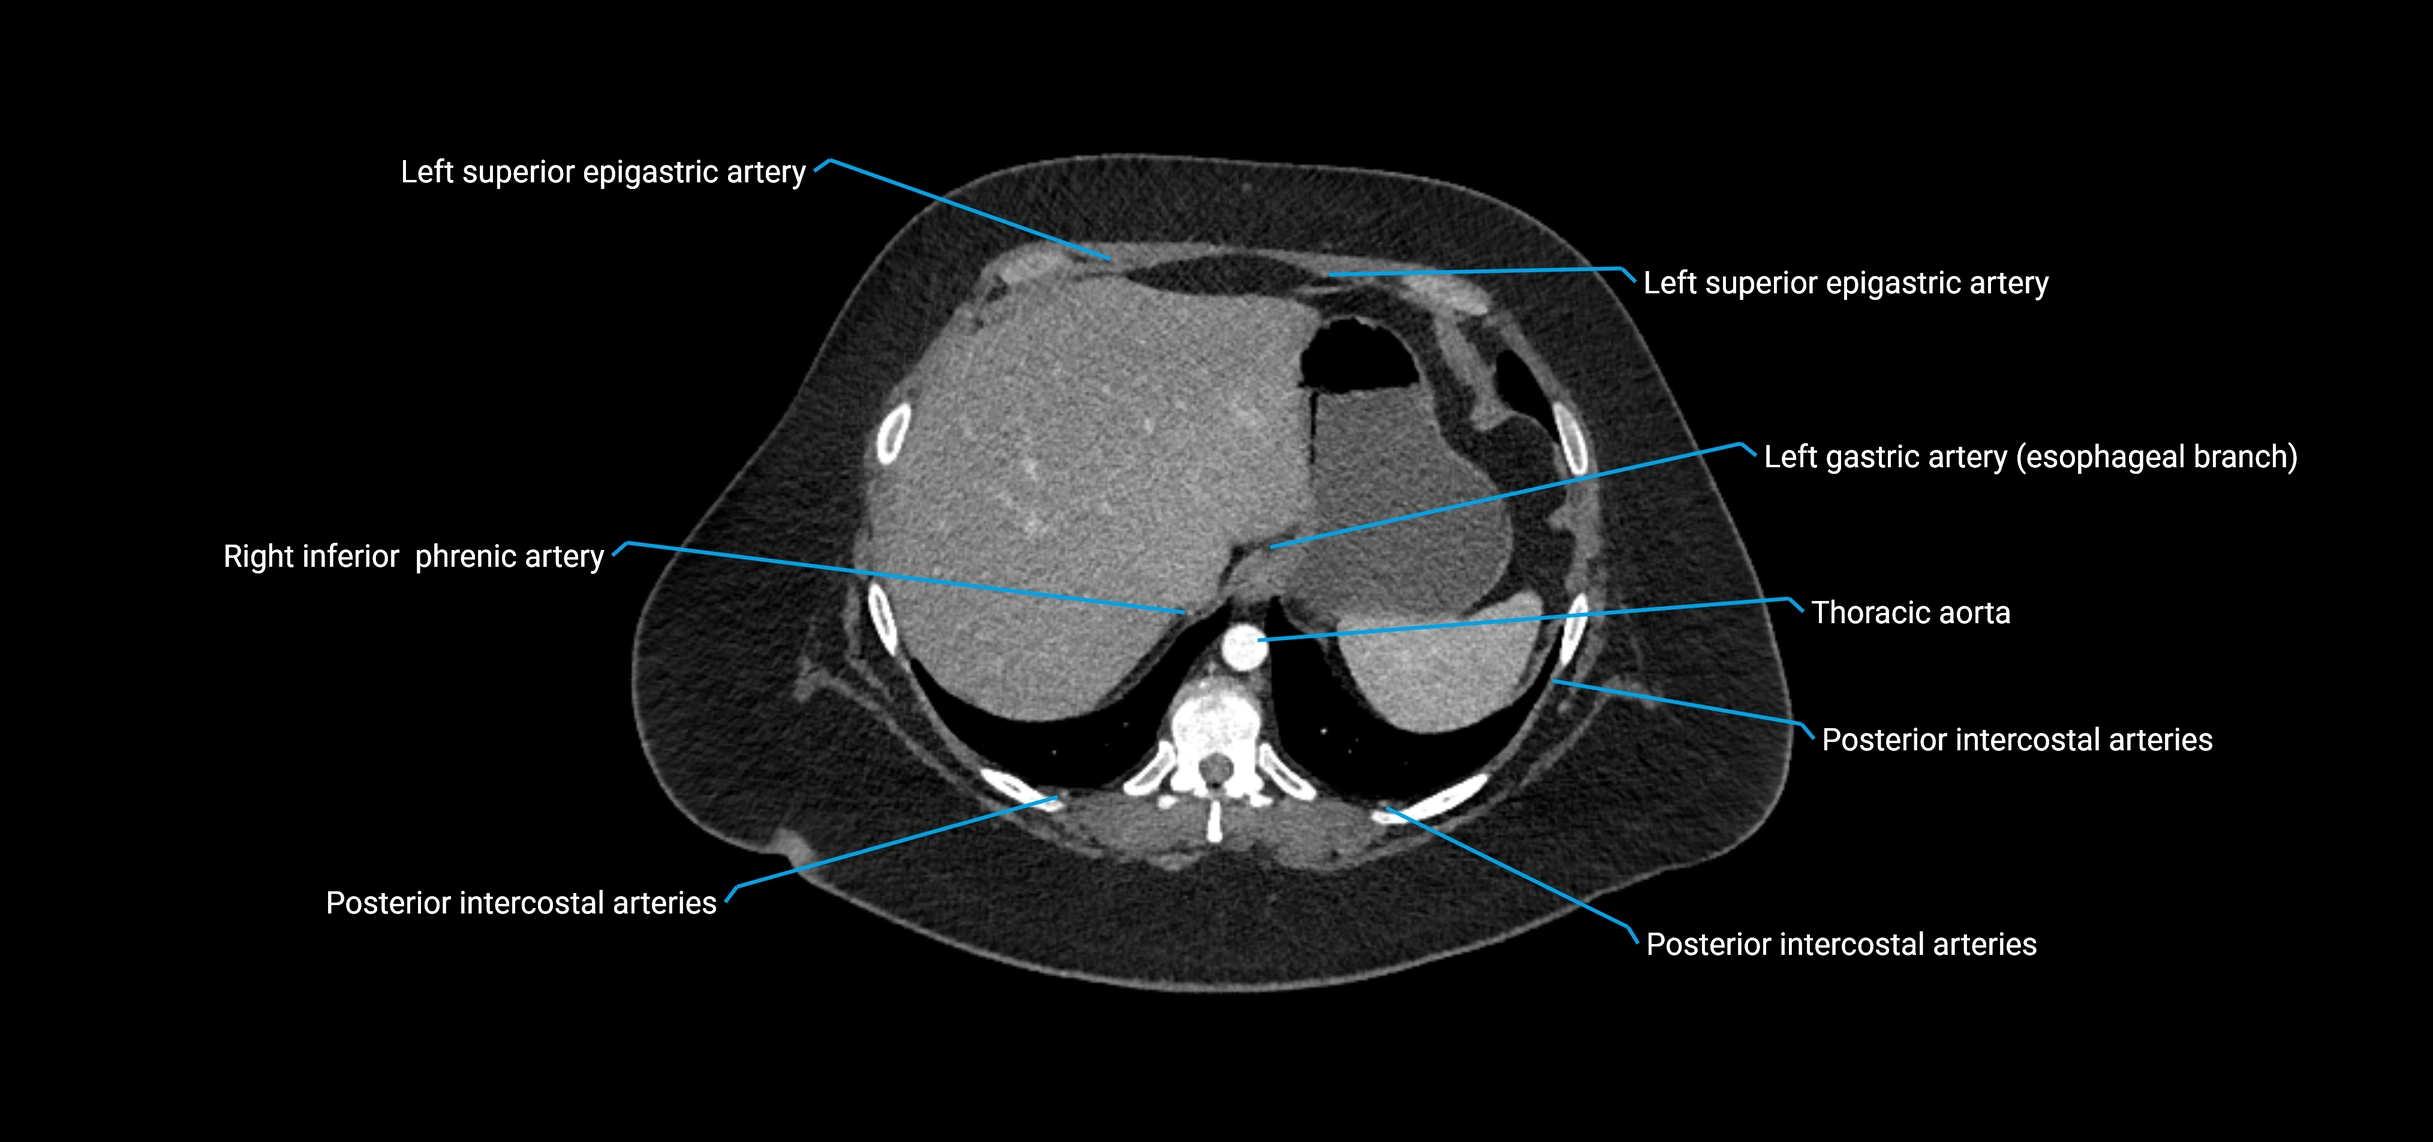

CT Appearance

Non-contrast CT:

• Appears as a tubular soft tissue structure anterior to vertebral bodies

• Calcified atherosclerotic plaques appear as hyperdense foci along the wall

• Useful for screening abdominal aortic aneurysm (AAA) size and mural calcification

Contrast-enhanced CT (CTA):

• Gold standard for abdominal aortic imaging

• Provides excellent detail of lumen, wall, aneurysm, thrombus, and branch vessels

• Multiplanar and 3D reconstructions help in aneurysm measurement, stent graft planning, and dissection evaluation

• Detects acute rupture, traumatic injury, or occlusion with high sensitivity